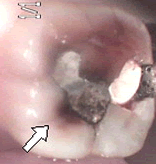

左の図の症例では、歯に何か染み込んでいるのがお解かりになるでしょうか?

これは、歯に詰められた、「アマルガム合金」と言う、水銀化合物が数年の間に溶け出し、歯の中の細い管の中に溶出して、やはり酸化して変色している症例です。

良く見ると、そのほかの部位にも淡い茶色い変色域が透けて見えています。そして、水銀合金の境目から、歯質の破折が起きて、穴が開いたようにも見受けられます。